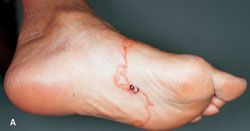

The plantar aspect of this toe shows purple nonuniform darkening that mimicked either a simple traumatic hematoma or the blue toe syndrome. More proximally, however, the solar aspect contained irregular dark-purple dots reminiscent of individual thrombosed venules, and in addition showed discontinuous purple zones more proximally in the part of the ray that lay within the body of the foot and that surely could not be imputed to any possible toe trauma or fracture nor to ischemia in the distribution of any single vessel. No purple area was warm or tender.